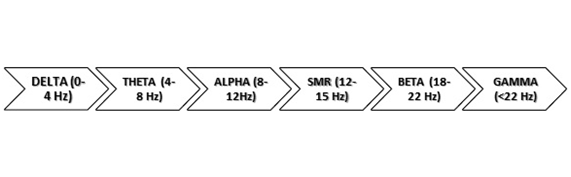

Los rangos de onda cambian en función del grado de actividad cerebral, predominando la menor (delta) cuando estamos dormidos y aumentando según va incrementándose la alerta.